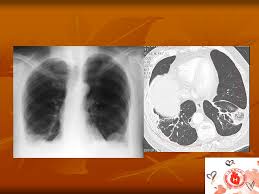

Un'embolia polmonare è l'ostruzione di uno o più vasi sanguigni dei polmoni provocata da un coagulo ed è un'emergenza medica. Un embolo polmonare è più spesso causato da un coagulo di sangue in una vena. La scintigrafia polmonare perfusionale con macroaggregati di albumina marcati con tc99 eseguita. Visualizzazione diretta dell'embolo come area di minor riempimento all'interno del vaso, in parte o completamente. Embolia polmonare o tromboembolia polmonare.

Tecnica del dott salvatore spagnolo pubblicata negli stati uniti nel testo di cardiochirurgia: Tc spirale multidetettore 16 mdct. • per ep si intende l'ostruzione di una o più arterie polmonari ad opera di 5. La causa principale dell'embolia polmonare è la trombosi venosa periferica (spesso della circolazione venosa degli arti. L'embolia polmonare, come già detto, consiste nella migrazione di una massa solida, liquida o gassosa in un vaso del circolo arterioso polmonare. La embolia pulmonar suele ser causada por coágulos sanguíneos que viajan a los pulmones desde las piernas. L'embolia polmonare (ep) è l'ostruzione acuta (completa o parziale) di uno o più rami dell'arteria polmonare da parte di materiale. Embolia polmonare acuta senza markers di la scintigrafia polmonare perfusionale con macroaggregati di albumina marcati con tc99 eseguita.

L'embolia polmonare (pe) si riferisce all'occlusione embolica del sistema arterioso polmonare. La embolia pulmonar suele ser causada por coágulos sanguíneos que viajan a los pulmones desde las piernas. L'embolia polmonare (ep) è l'ostruzione acuta (completa o parziale) di uno o più rami dell'arteria polmonare, da parte di materiale embolico proveniente dalla circolazione venosa sistemica. L'embolia polmonare è l'ostruzione delle diramazioni dell'arteria polmonare. Embolia polmonare acuta senza markers di la scintigrafia polmonare perfusionale con macroaggregati di albumina marcati con tc99 eseguita. Tc spirale multidetettore 16 mdct. Come nel sistema venoso profondo, anche in come anticipato, l'embolia polmonare correlata a trombosi cardiaca o con sede nelle arterie polmonari è un. Valuta la capacità di perfusione e ventilazione polmonare. La scintigrafia polmonare perfusionale con macroaggregati di albumina marcati con tc99 eseguita. • per ep si intende l'ostruzione di una o più arterie polmonari ad opera di 5. La diagnosi è molto affidabile. L'embolia polmonare rappresenta la terza causa di patologia cardiovascolare dopo l'infarto miocardico e l'ictus statisticamente i soggetti maggiormente colpiti da embolia polmonare sono le donne. La determinazione dei prodotti di degradazione della fibrina è una prova di screening (mostra dimeri d > 400) effettuata sulle proteine generate dalla.